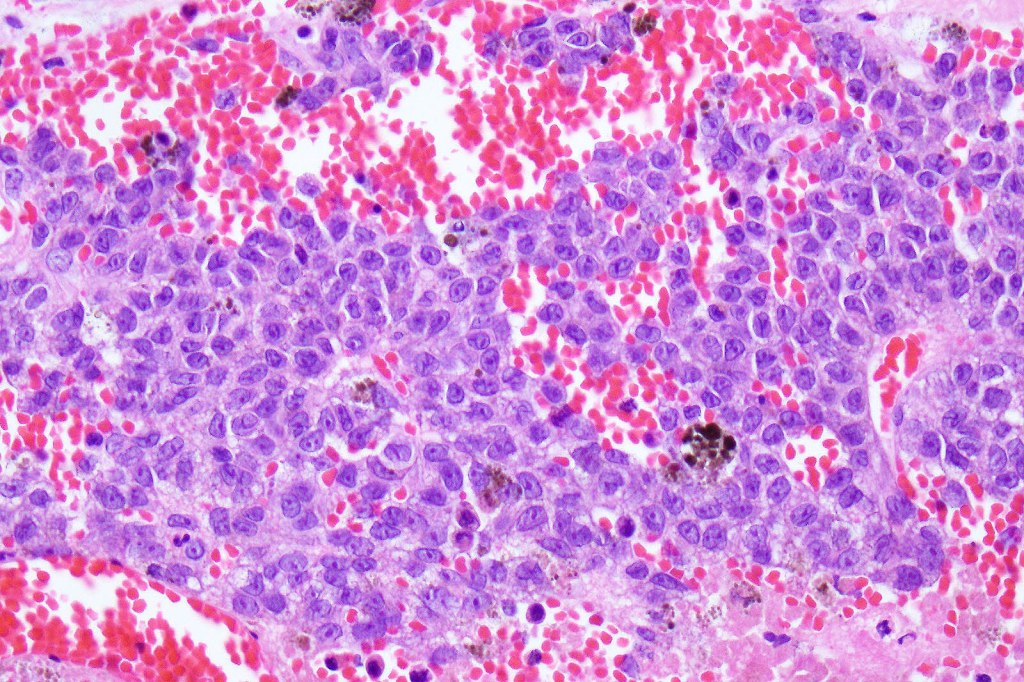

•Typical melanoma, nevoid melanoma, small cell melanoma, pleomorphic/anaplastic melanoma, melanoma with heterologous differentiation & malignant nerve sheath-like melanoma.

This melanoma arose in a small congenital nevus of the scalp. It metastasized widely. Varying features in different fields.